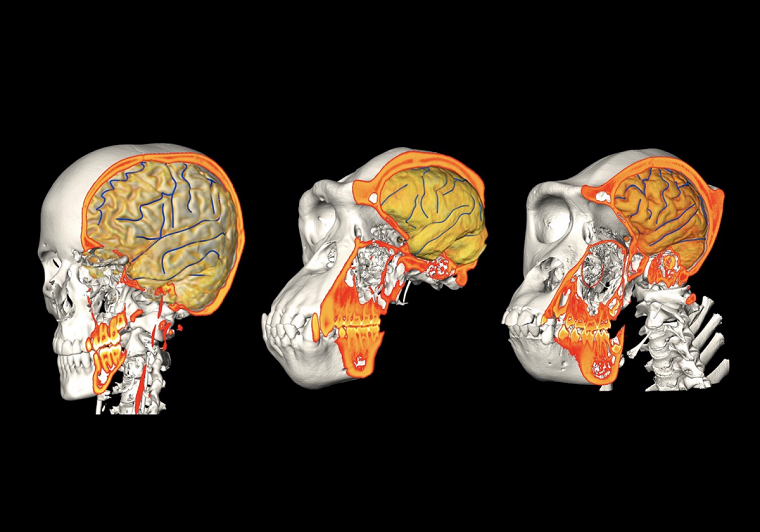

Здоровый человеческий мозг в зрелом возрасте обычно достигает 1500 см³, что примерно в три раза больше, чем мозг гориллы (500 см³) или мозг шимпанзе (400 см³). В рамках исследования команда Кембриджского университета собрала клетки людей, горилл и шимпанзе, оставшиеся после медицинских тестов и операций, и перепрограммировала их в стволовые клетки. Затем ученые вырастили эти клетки таким образом, чтобы превратить их в органоиды мозга — небольшие комочки мозговой ткани шириной в несколько миллиметров.

По мере созревания клеток их деление замедляется. Как указывает доктор Мадлен Ланкастер из Кембриджского университета, клетки-предшественники человеческого мозга дольше задерживаются на ранней стадии развития, чем клетки мозга обезьяны, и за это время чаще делятся. Эта разница в конечном итоге приводит к почти удвоенному числу нейронов в коре головного мозга взрослого человека по сравнению с мозгом человекообразных обезьян.